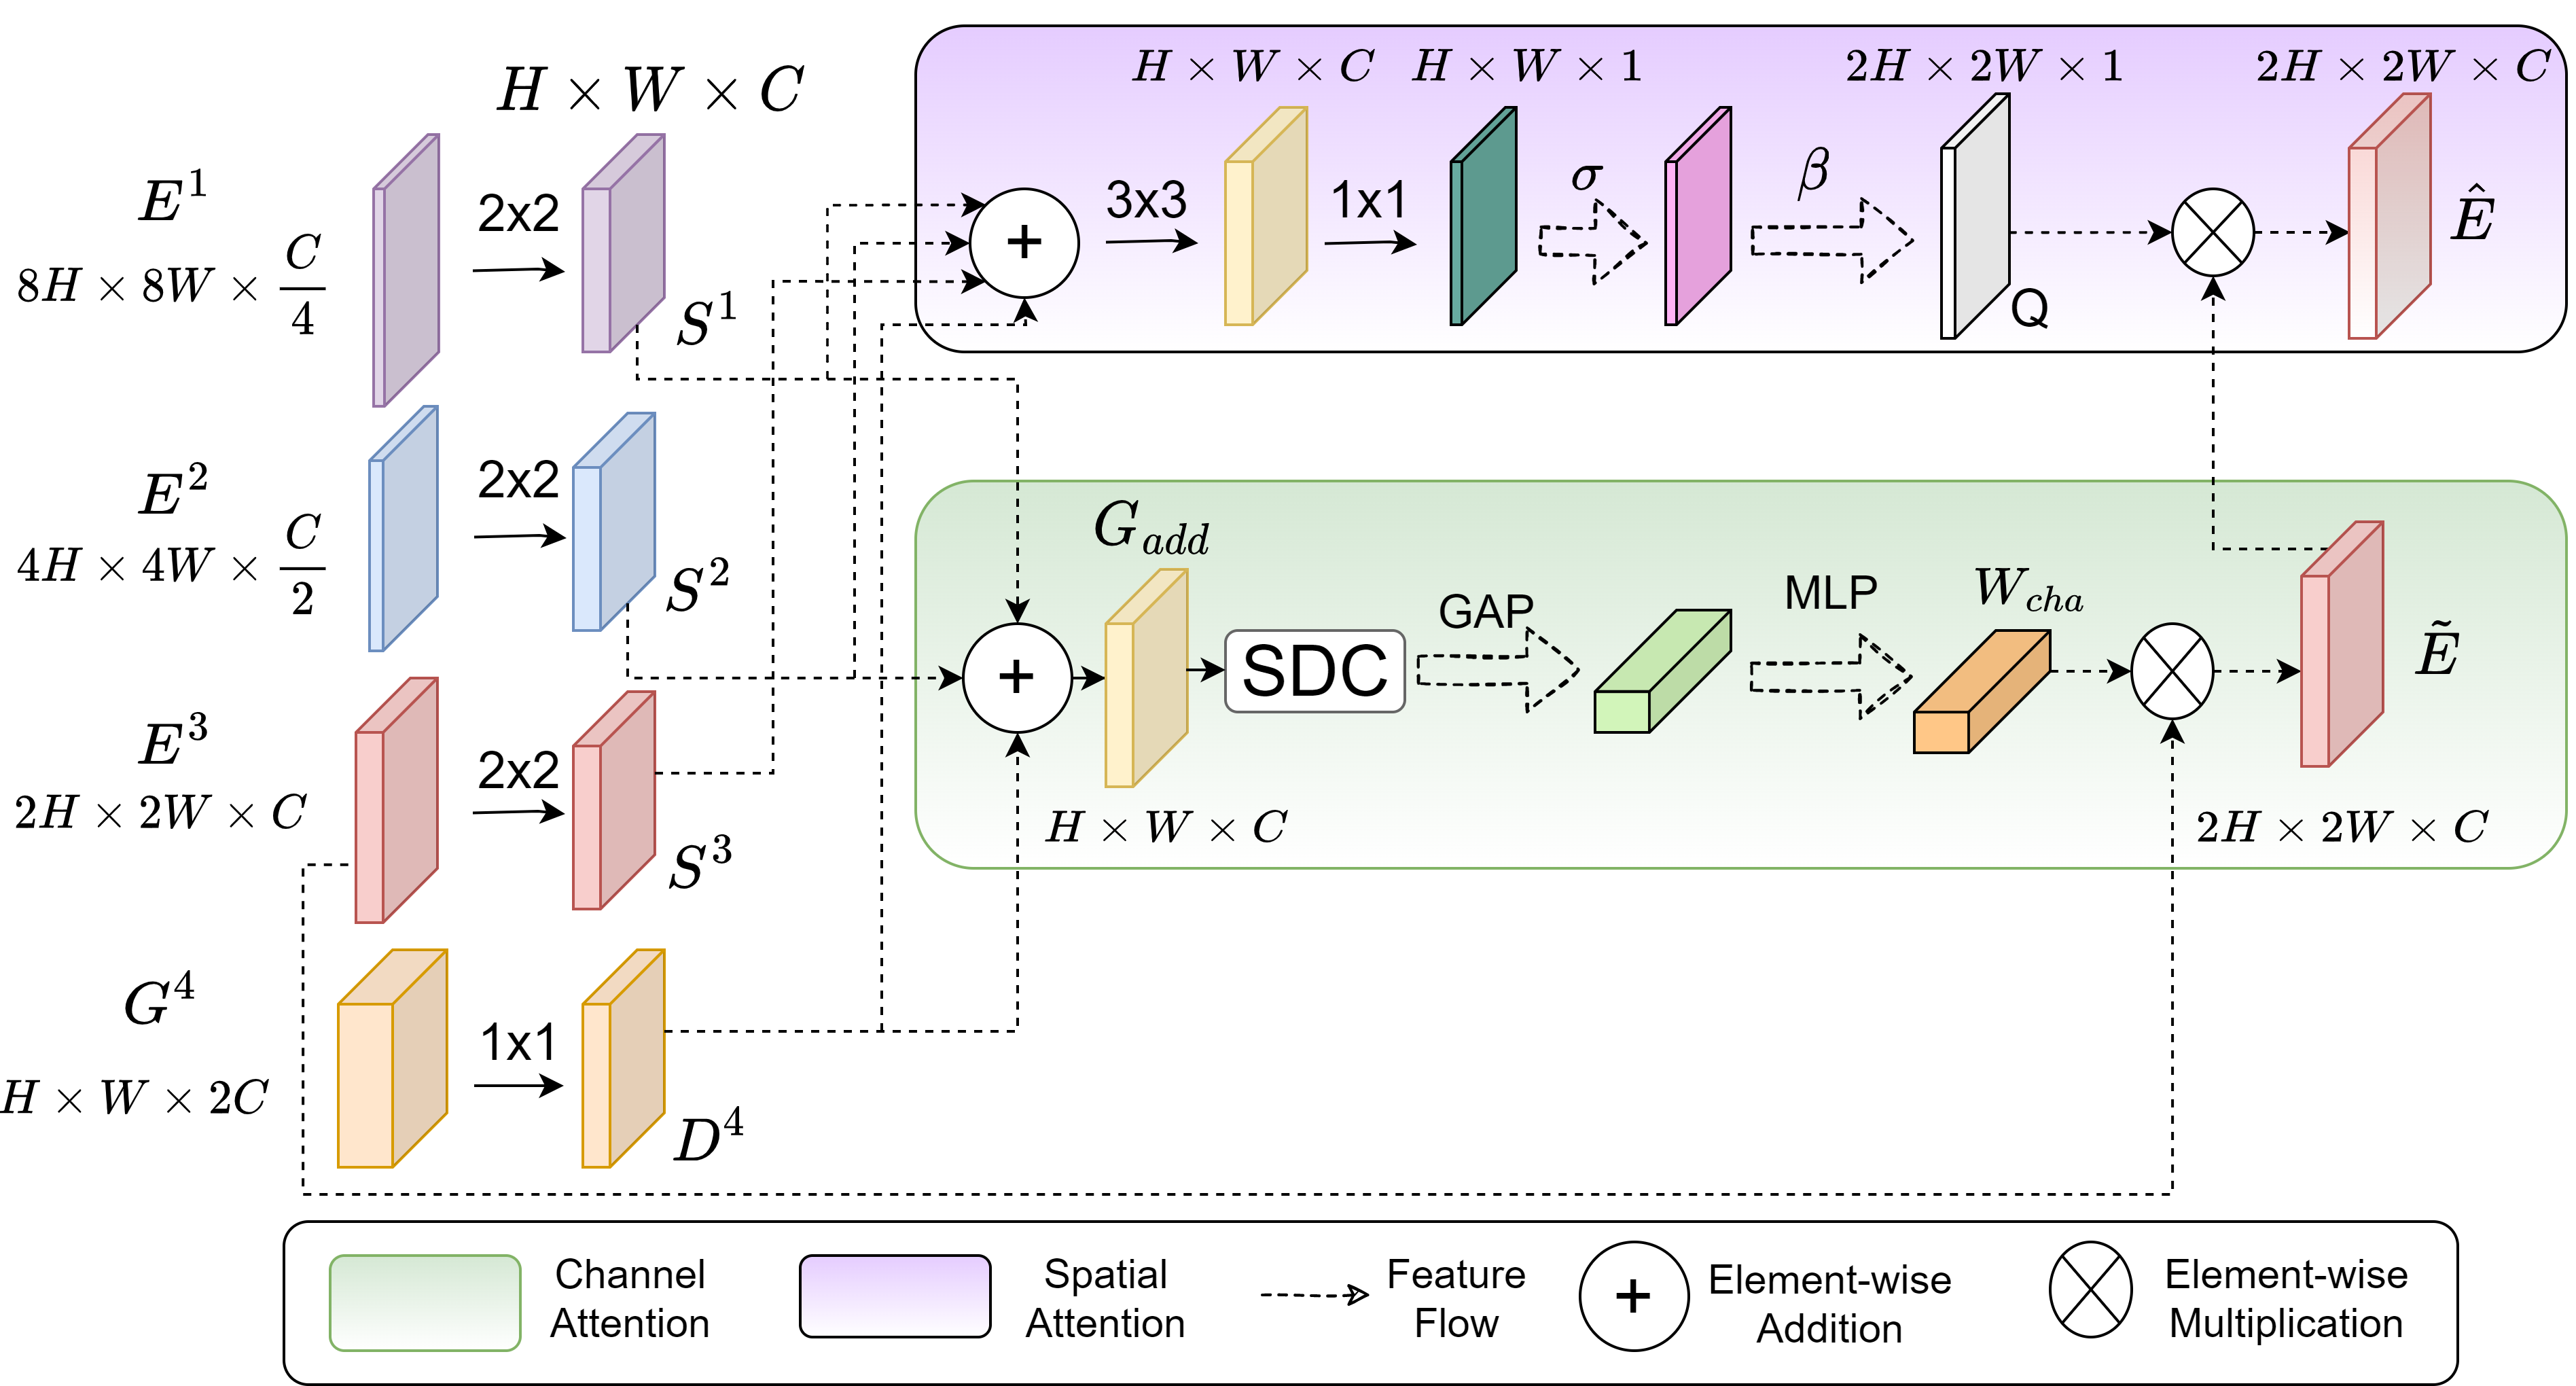

The proposed Full-scale Deeply Supervised Attention Network (FuDSA-Net), depicted in Fig. 1, is built on the standard encoder-decoder framework of the -Net. The skip connections are redesigned by incorporating the novel attention module at each level . Additionally, the connections within the decoder arm are restructured to enable each layer to receive accumulated knowledge from all its preceding blocks. This mechanism promotes enhanced feature propagation along the entire decoding path, with minimal loss of information. Deep supervision, applied throughout the decoder, helps learn discriminative patterns at all transitional levels.

Fig. 2 illustrates how the attention module generates the recalibrated output volume, at the third level of the network, from the encoder volume . The input to the attention module (at level ) is a collection of activation maps from all preceding levels of the encoder arm (up to ), encompassing full multi-scalar information expressed as and the output volume of the decoder from level which is . To maintain consistency across the input response maps from the encoder, over multiple scales, we perform a convolution on the high-resolution maps to obtain the set of maps ; thereby, reducing their spatial and channel dimensions until they are of the same dimensions as the lower-resolution maps. The decoder volume also undergoes a point-wise convolution to shrink its number of channels from to . The resultant decoder volume is denoted as .

The maps are element-wise added (), along the channel attention branch, to produce an intermediate resultant volume expressed as

| (1) |

Next a block of several stacked dilated convolution (SDC) kernels, having varying dilation rates, is applied to . This allows multi-scalar receptive fields, with the benefit of learning at various resolutions, by widening the kernel size without increasing the total number of parameters. Global Average Pooling (GAP) condenses the global information present in each map of the resultant volume into a tensor. This is passed through a multi-layer perceptron (MLP) with sigmoid activation function and RELU to generate the final weight tensor , to be point-wise multiplied () with the encoder map (at level ) to yield . We have

| (2) |

| (3) |

Let us now consider the spatial attention component. Here the input maps are pixel-wise added, followed by a convolution to learn features from the intermediate outputs. Next the resultant volume is convolved with kernels , followed by activation and upsampling operation to generate the spatial attention map as

| (4) |

The final output of the attention module is generated, as a combination of the channel and spatial attention components of eqns. (3) and (4), as

| (5) |